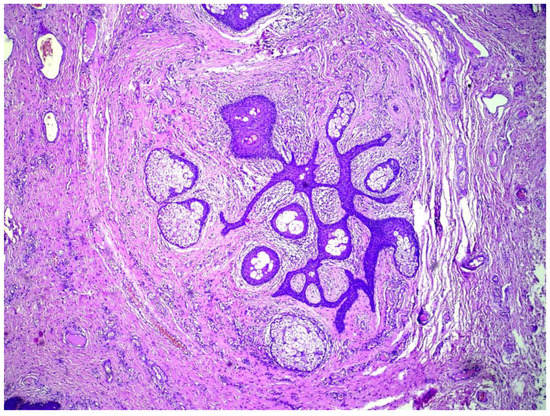

2. Detailed Case Description